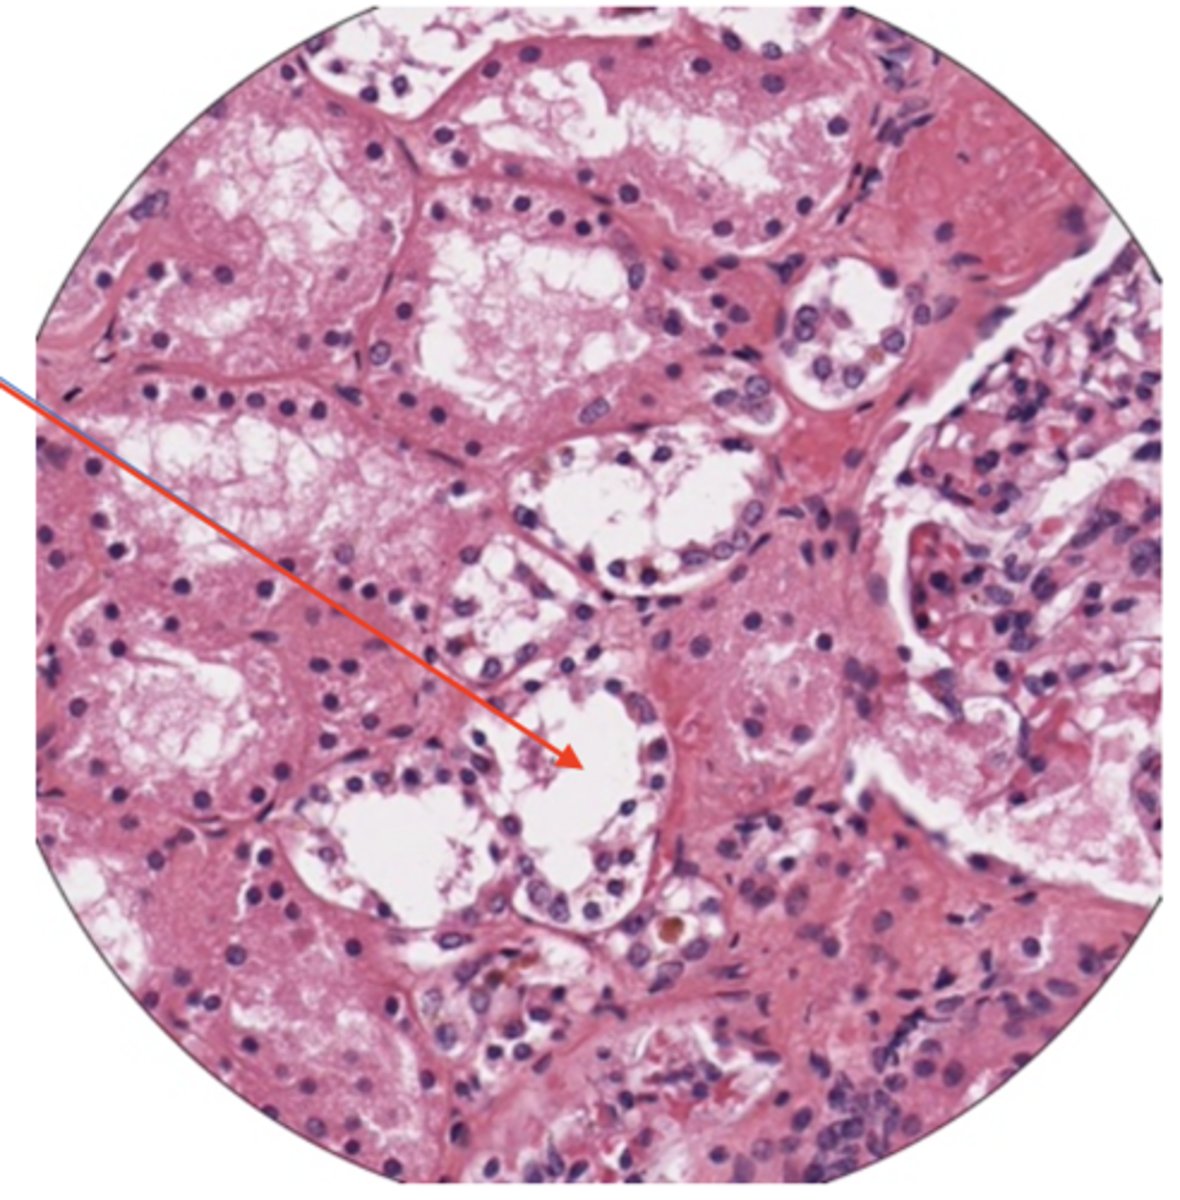

glomerulus

convoluted tubules

collecting duct